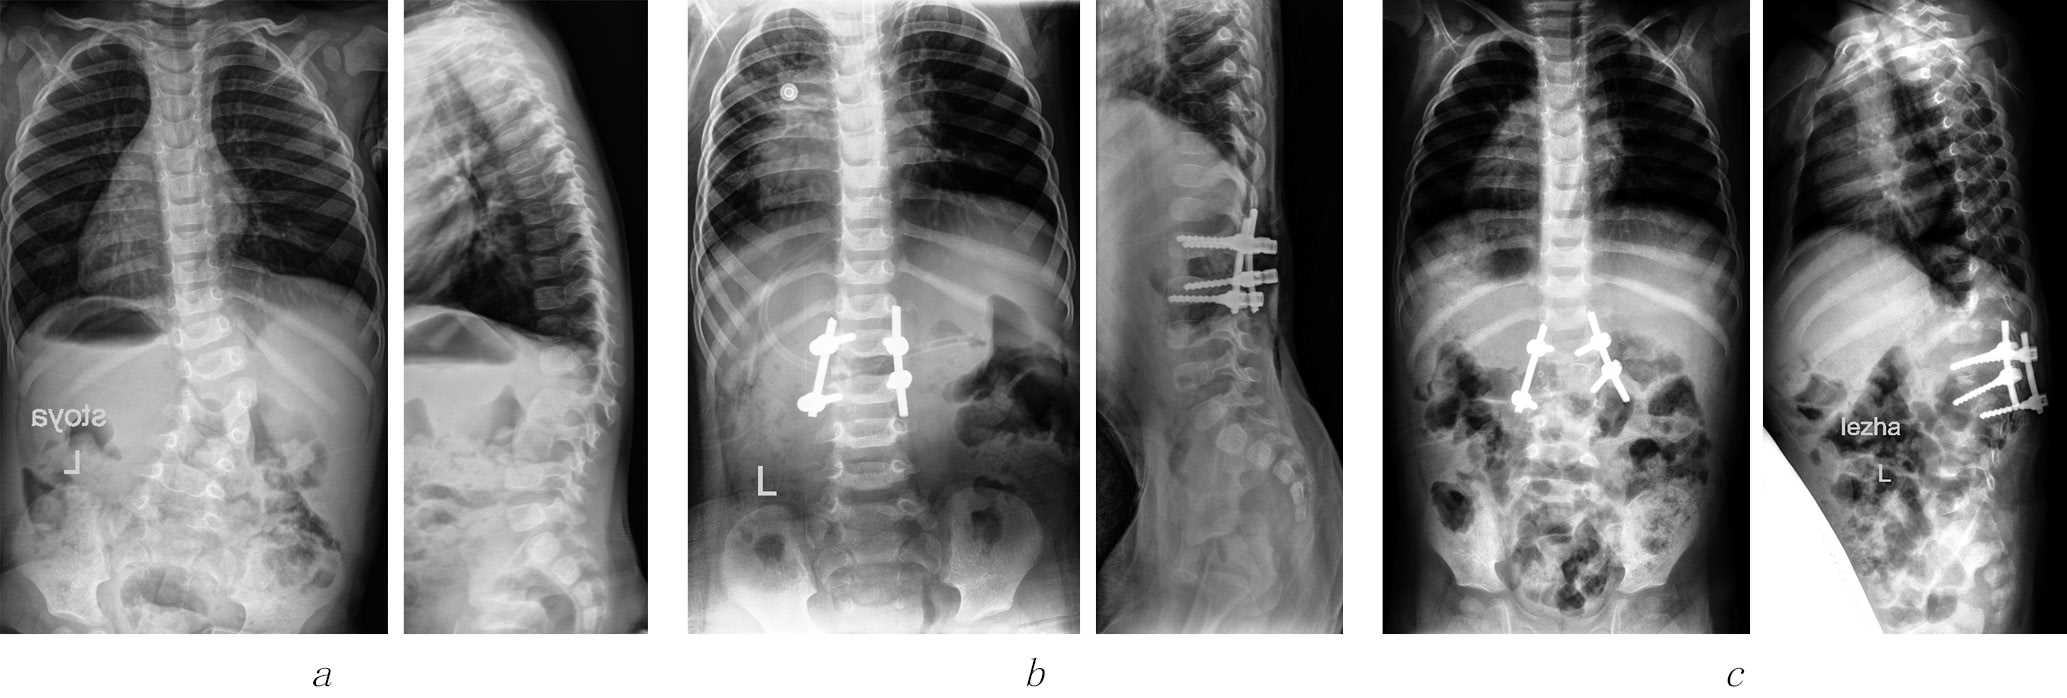

Рентгенограммы пациента С., 1 год 9 мес., с врожденным кифосколиозом поясничного отдела позвоночника на фоне заднебокового полупозвонка L2: a — до операции угол сколиоза — 39°, угол кифоза — 26°; б — после экстирпации полупозвонка из комбинированного доступа и коррекции врожденной деформации; в — дестабилизация металлоконструкции

Необходимо отметить, что у всех пациентов с врожденной деформацией позвоночника в зоне порока зафиксированы выраженные значения сколиотического и/или кифотического компонентов искривления (см. табл. 1). Во время корригирующих манипуляций это обусловливало значительное давление транспедикулярных винтов на костные структуры тел позвонков. Несмотря на то что часть опорных элементов была установлена корректно, достаточно небольшая протяженность металлофиксации и малые размеры основания дуг позвонков способствовали прорезыванию основания дуг и сминанию костных балок тел позвонков, что и приводило к дестабилизации спинальной системы (см. рисунок).

В сроки от 3 до 6 мес. после операции у всех детей исследуемой группы родители отмечали ухудшение в виде появления искривления позвоночника в зоне вмешательства. Наблюдались асимметрия треугольников талии, разная высота стояния углов лопаток, наличие мышечного валика. Это служило поводом для обращения в стационар и проведения контрольного обследования. После выполнения лучевого исследования выявлены смещение опорных элементов спинальной системы относительно основания дуги позвонка, прорезывание костных структур основания дуг и тел позвонков в зоне транспедикулярных опорных элементов, а также потеря коррекции деформации позвоночника, которая достигала от 15 до 44° по Коббу (М = 25 ± 5,7°).